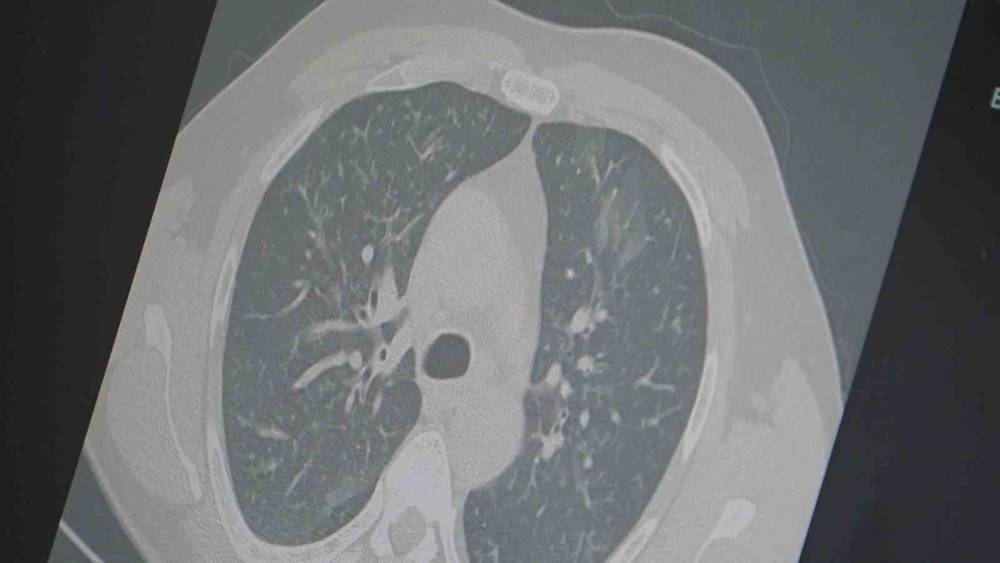

Dr. Özkaya, grip ve kovid 19’un zatürreye dönüşme riski taşıdığını vurgulayarak, "Grip veya kovid sonrası birçok hastamızda hastalık akciğerlere iniyor ve zatürre olarak karşımıza çıkıyor. Hastaneye yatan hasta sayısında da artış gözlemliyoruz" şeklinde konuştu.